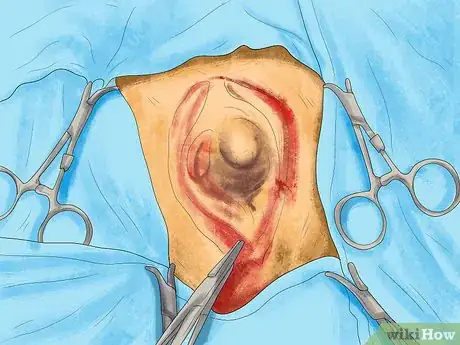

3Allow your vet to do tests. Your vet will likely be able to determine whether a particular lump is fluid-filled, such as an abscess, or is solid, such as a tumor or cyst. However, they will not be able to determine whether a tumor is harmless or dangerous without doing tests. They will likely need to use a needle or scalpel to remove a small amount of tissue from the lump and test it in a lab.

4Agree to a biopsy. Your vet will recommend a biopsy if they are not able to determine the cause of a lump through initial tests. Your cat will be anesthetized so that part or all of the lump can be removed. This is worthwhile, as it allows your vet to get a definitive diagnosis on the cause of the lump.